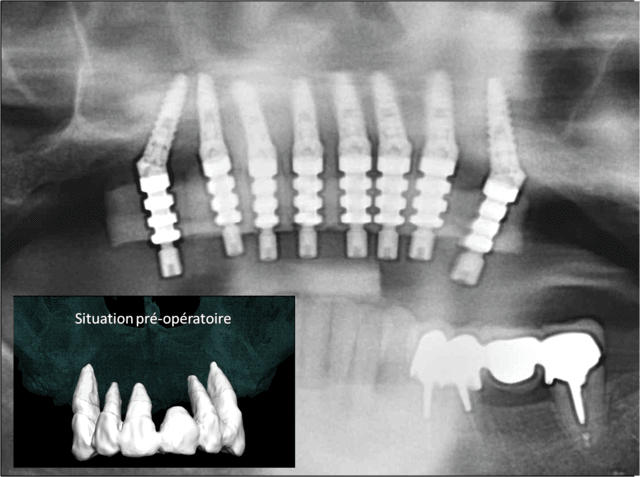

19/02/2013 à 19h28

posit écrivait:

---------------

> Chirurgie guidée programmée pour lundi

>

> Extraction, implantation, mise en charge immédiate avec bridge provisoire à

> armature métal.

> Extraction : 13, 12, 11, 22, 23.

> Implants : 8 implants Ø3,75 longueur 13 mm, angulation 30°, position 15, 13,

> 12, 21, 22, 23, 25.

> Simulation implantaire assistée par ordinateur en 3D.

> Guide chirurgical en acier juxta-osseux.

> Dispositif de forage spécifique.

> Provisoire : armature en en acier chirurgical 10 dents de 15 à 25.

> Définitif programmé : bridge transvisé 12 dents de 16 à 26.

> Image S.I.A.O

suivie radiographique à 1 an de ce cas clinique

Protocole de mise en charge imm diate positdental 008 c7zle0 - Eugenol